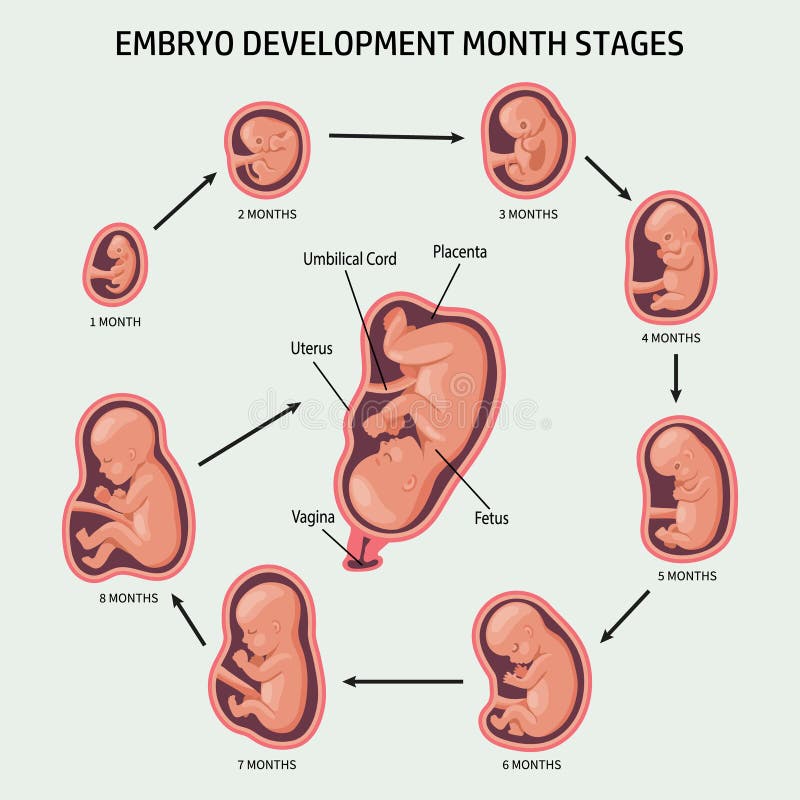

Looking for captivating what does a 2 month old fetus look like images? All, in collaboration with felix.edu.vn, presents a curated selection. Dive into the details for more.

what does a 2 month old fetus look like

Posts: what does a 2 month old fetus look like